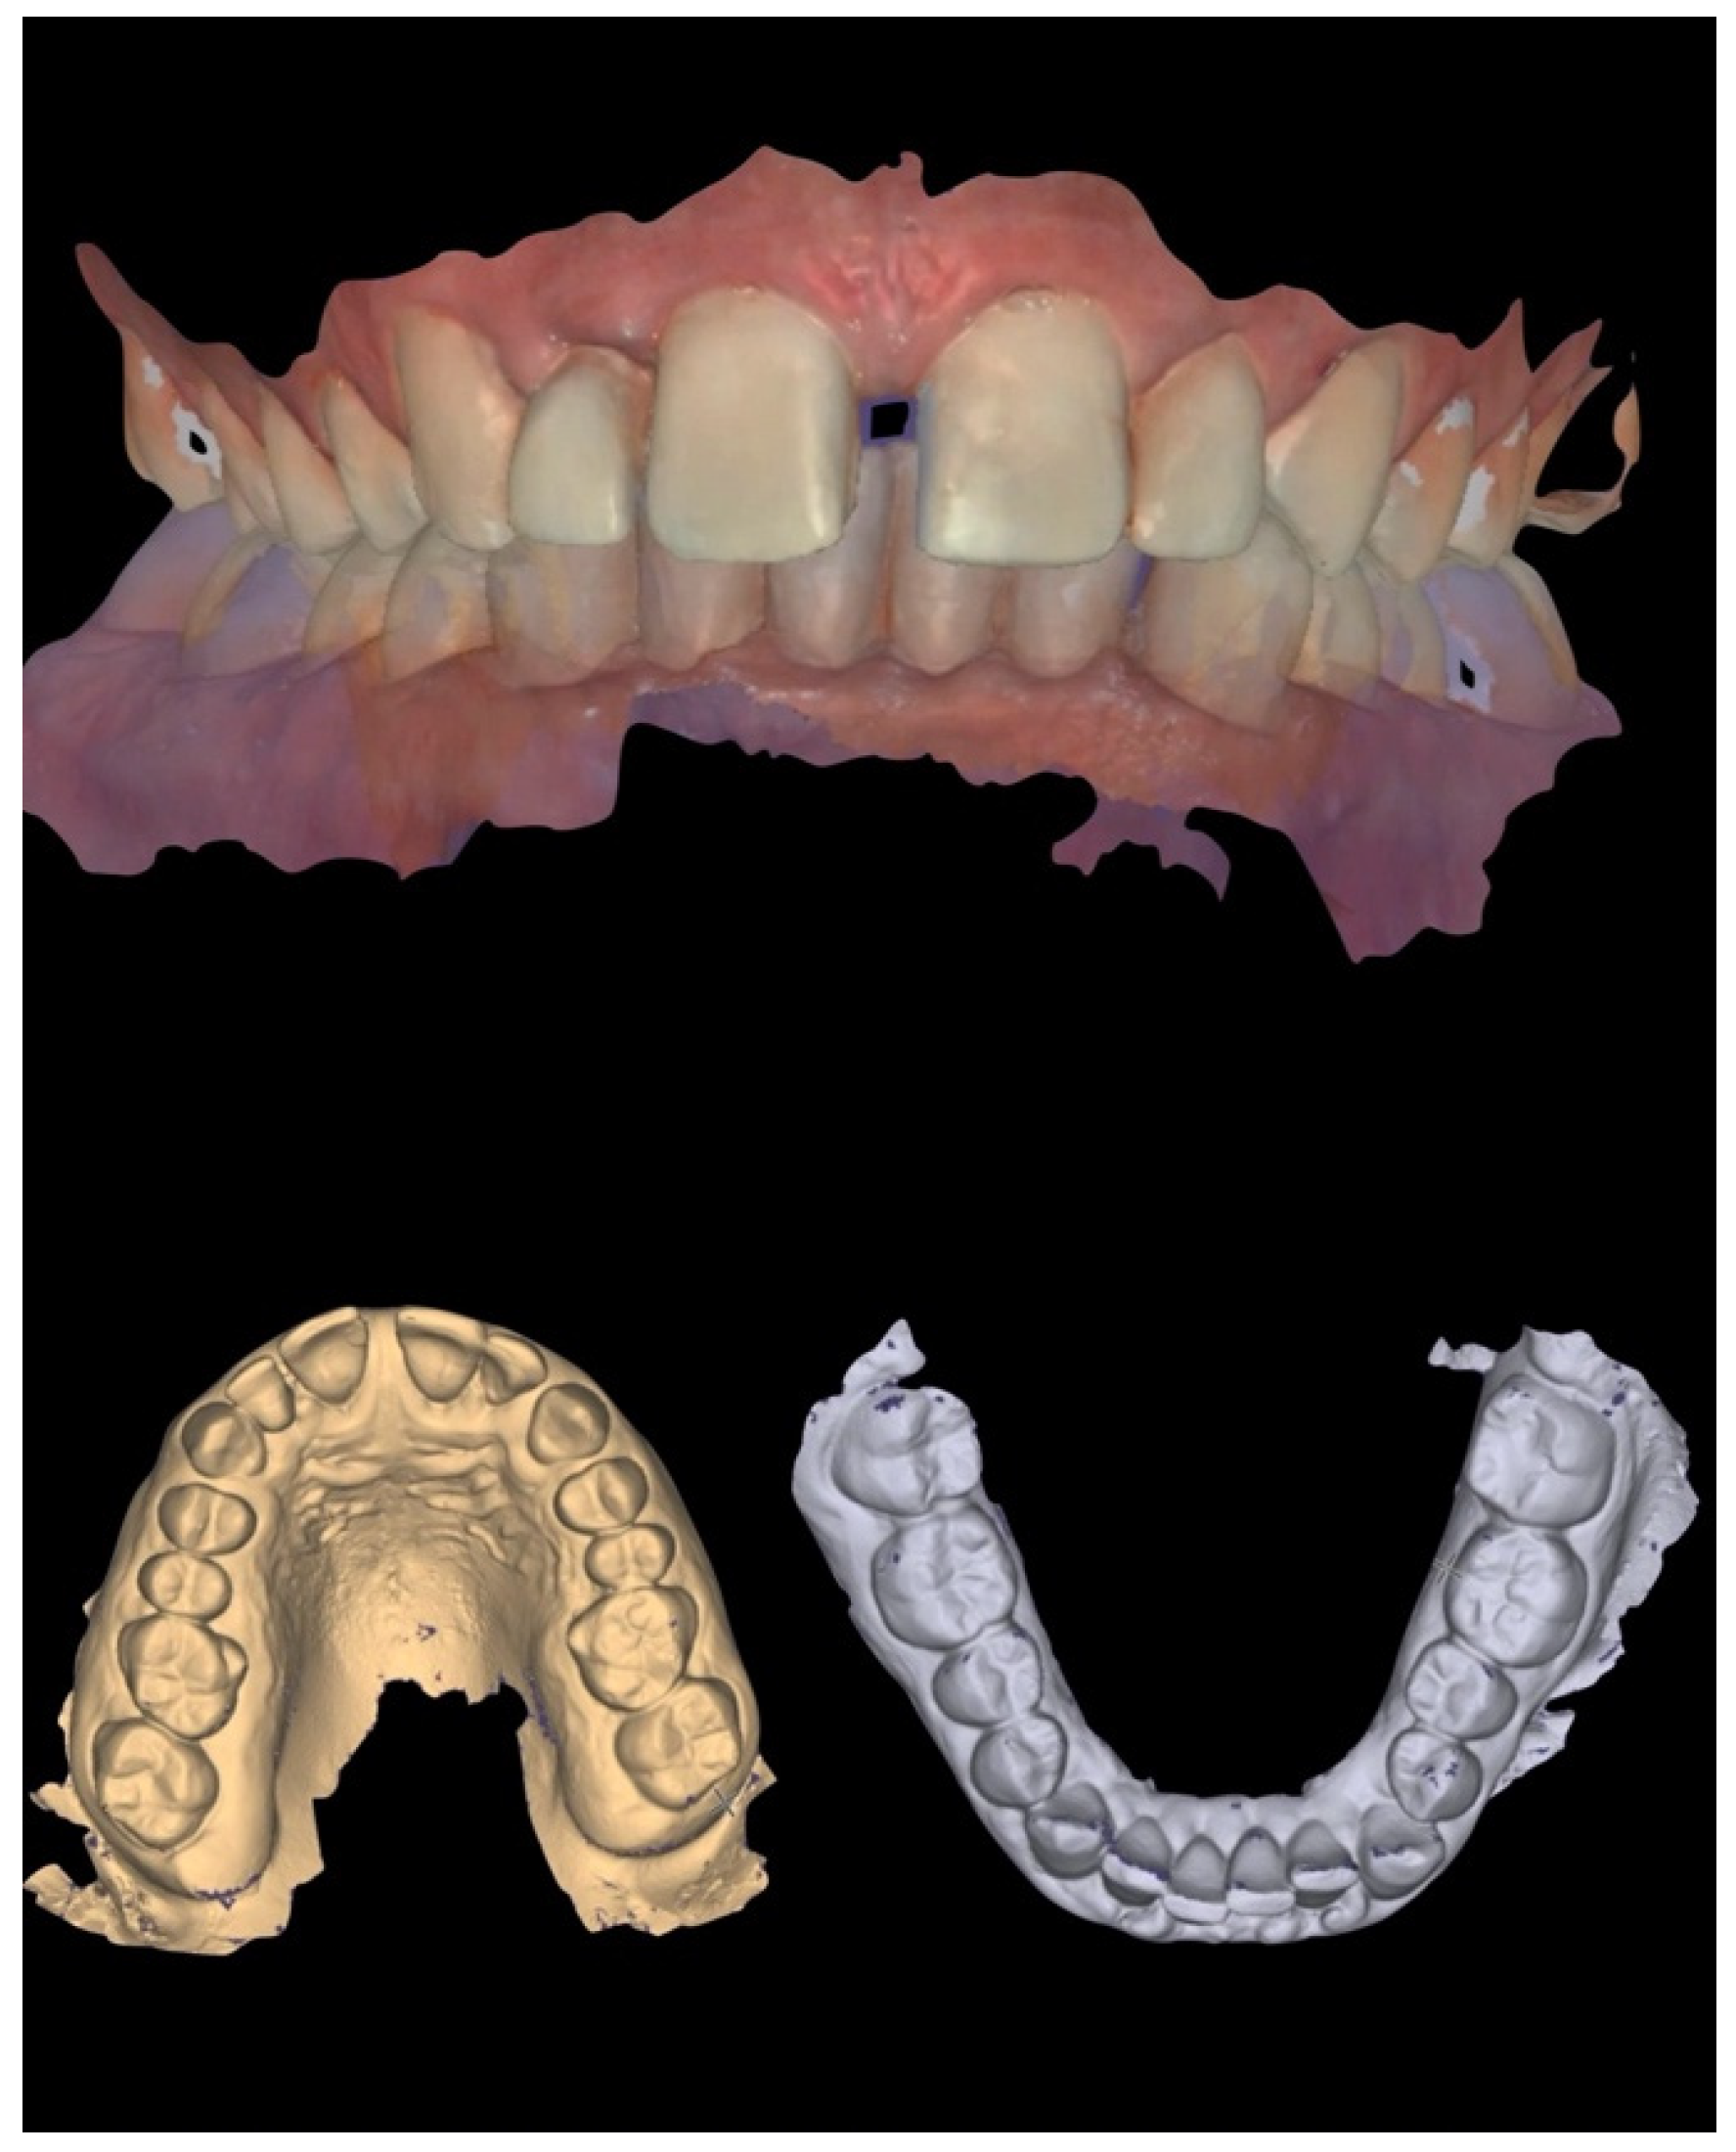

Initial periodontal therapy was performed to control inflammation and halt disease progression by removing supra- and subgingival plaque and calculus through professional cleaning (scaling and root planing), improving oral hygiene habits, and managing risk factors such as smoking and diabetes. A provisional restoration was then designed through a digital laboratory workflow (CAD—Smile Creator) (Figure 7) to simulate the final outcome and evaluate whether to maintain the interincisal diastema.

Figure 7. Laboratory workflow (CAD)—Smile Creator.

Since the patient declined orthodontic treatment, a pre-preparation provisional was fabricated to preserve the diastema, reduce overbite, and improve both anterior guidance and posterior group function. The initial extraoral photos with and without retractors were imported in exocad and converted to 3D objects, which can be matched to 3D scans of the teeth. Tooth shapes were selected from an extensive library and edited by using dedicated editing tools. Highly realistic AI-based (artificial intelligence) smile makeover visualisations (exocad’s DentalCAD 3.2 Elefsina, TruSmile Video, exocad GmbH) based on individual tooth setups and treatment plans were obtained and discussed with the patient. Provisional restorations were fabricated by CAD/CAM milling in polymethyl methacrylate (PMMA) (Figure 8).

Figure 8. Laboratory workflow (CAD)—milled PMMA provisional restorations.